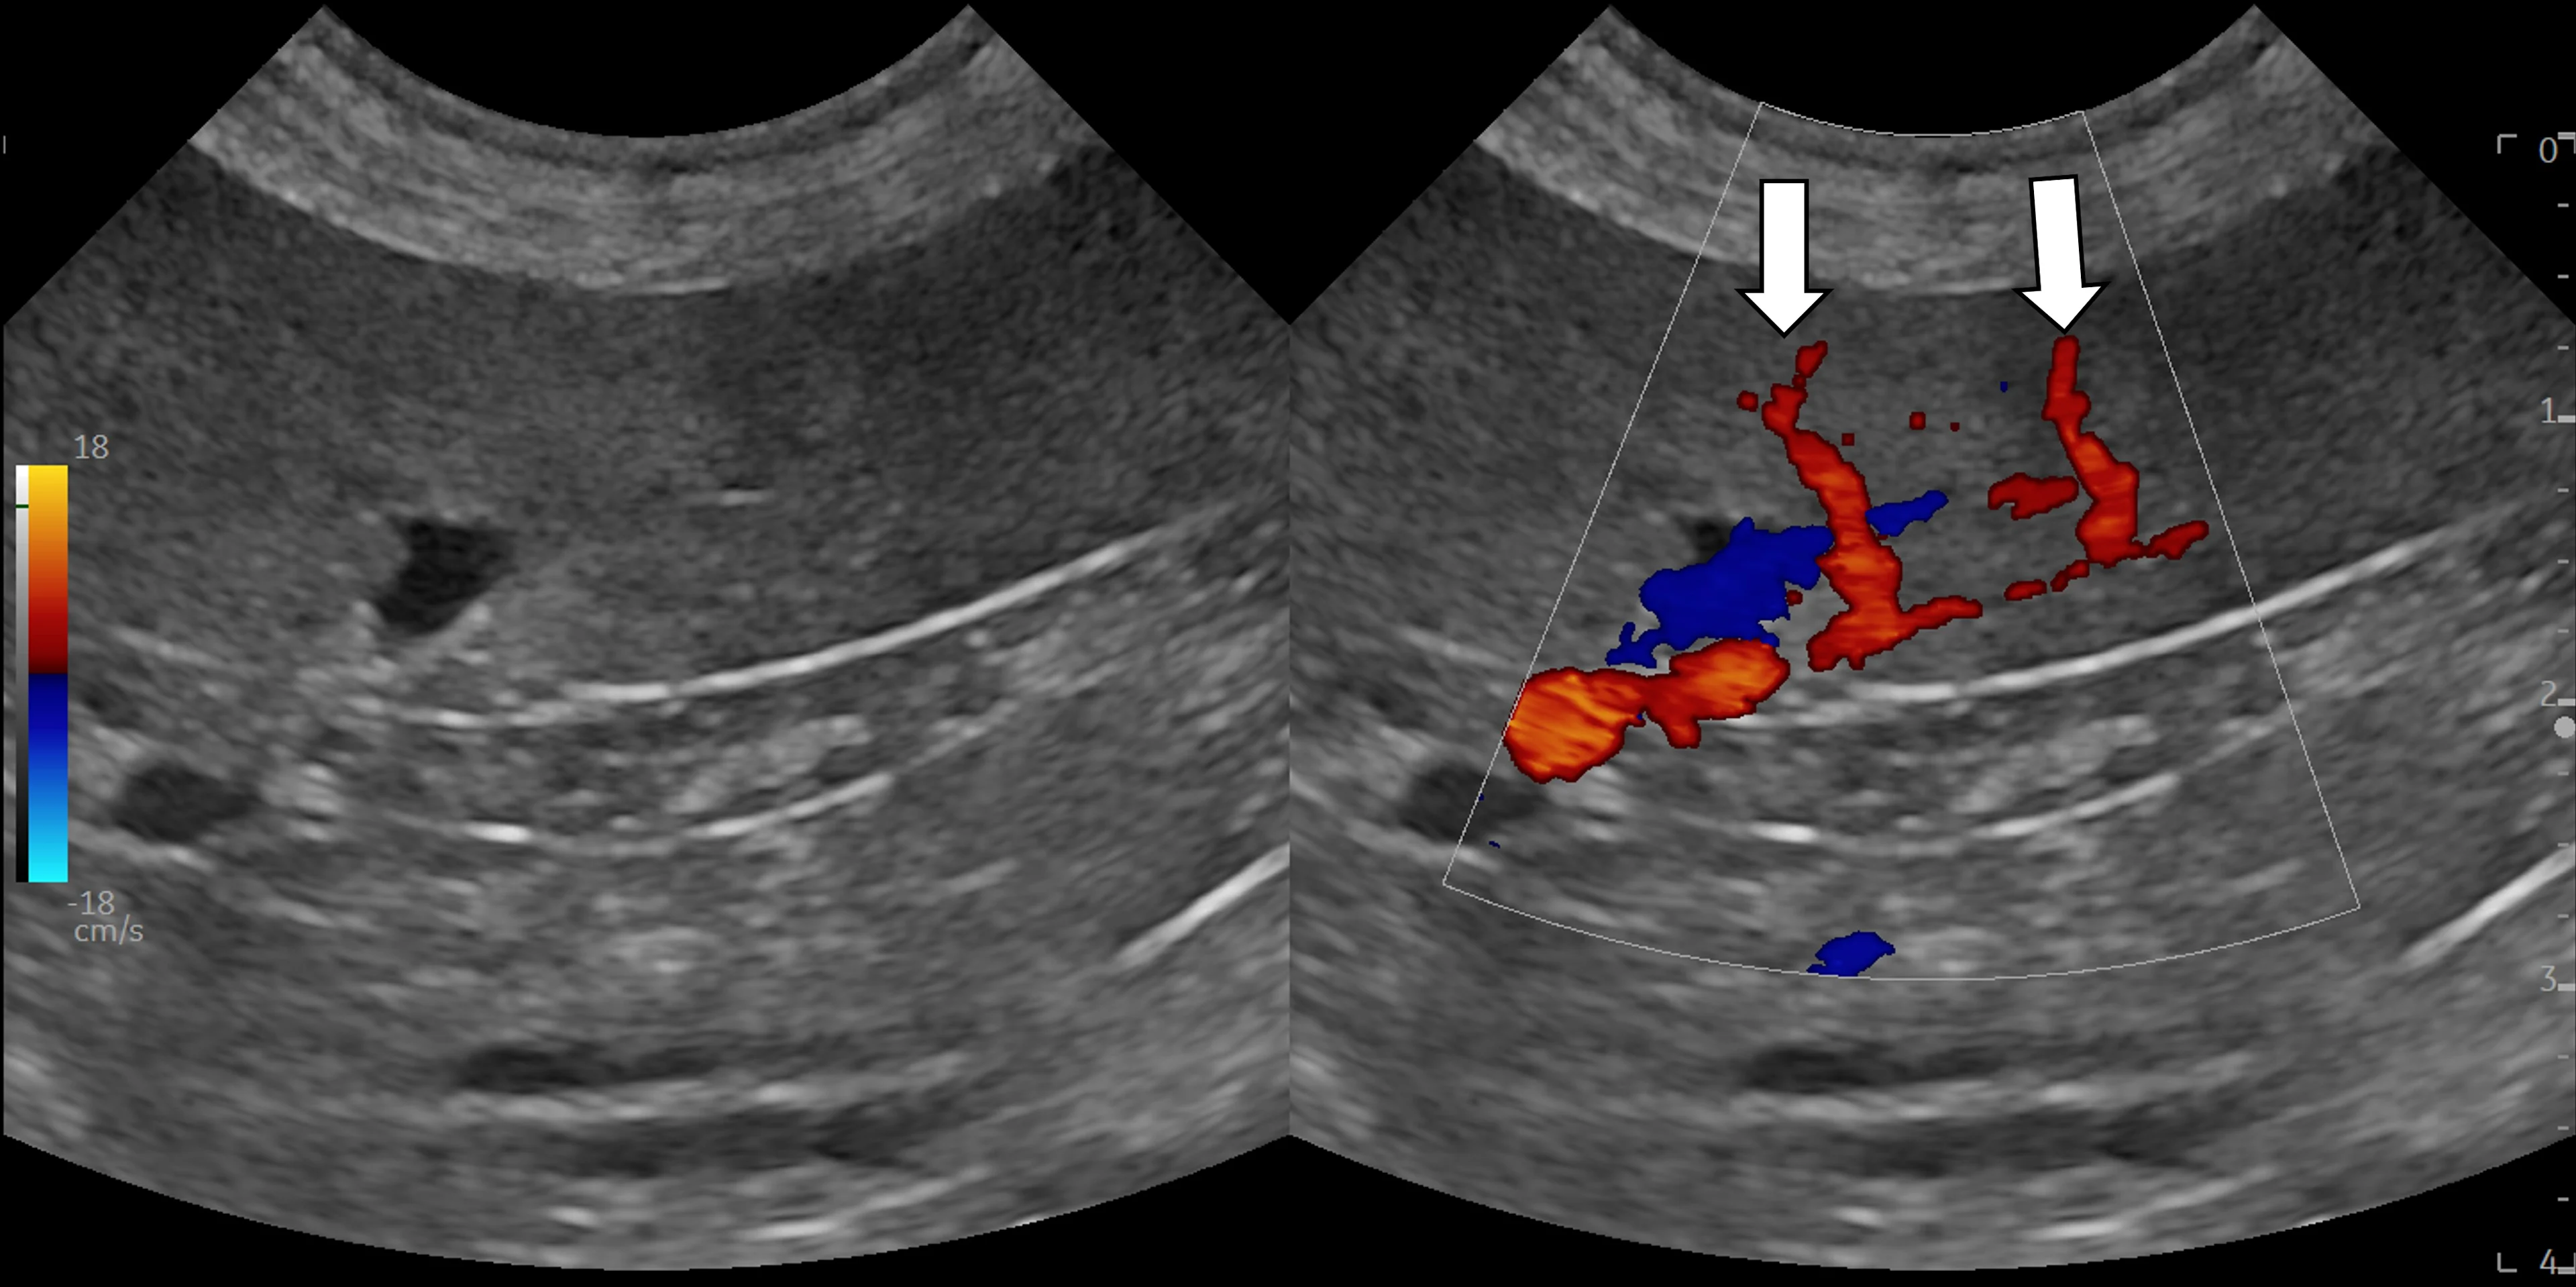

Interrogate the target and adjacent structures with gentle fanning/sweeping and rocking/sliding of the transducer in both planes. Attempt to identify the ideal window and travel path that will allow the needle to pass through the skin and directly into the lesion of interest while only passing through the peritoneal or retroperitoneal space. Avoid vessels, other organs, and separate body regions/cavities. If available, interrogate the lesion and surrounding area with color or power Doppler (see Video) to help identify vessels that may not be visible with brightness mode (B-mode) alone.

Color Doppler identifies 2 splenic arteries (arrows) extending toward the periphery. These vessels were not easily seen on B-mode and may have been punctured if sampling was performed in this area.